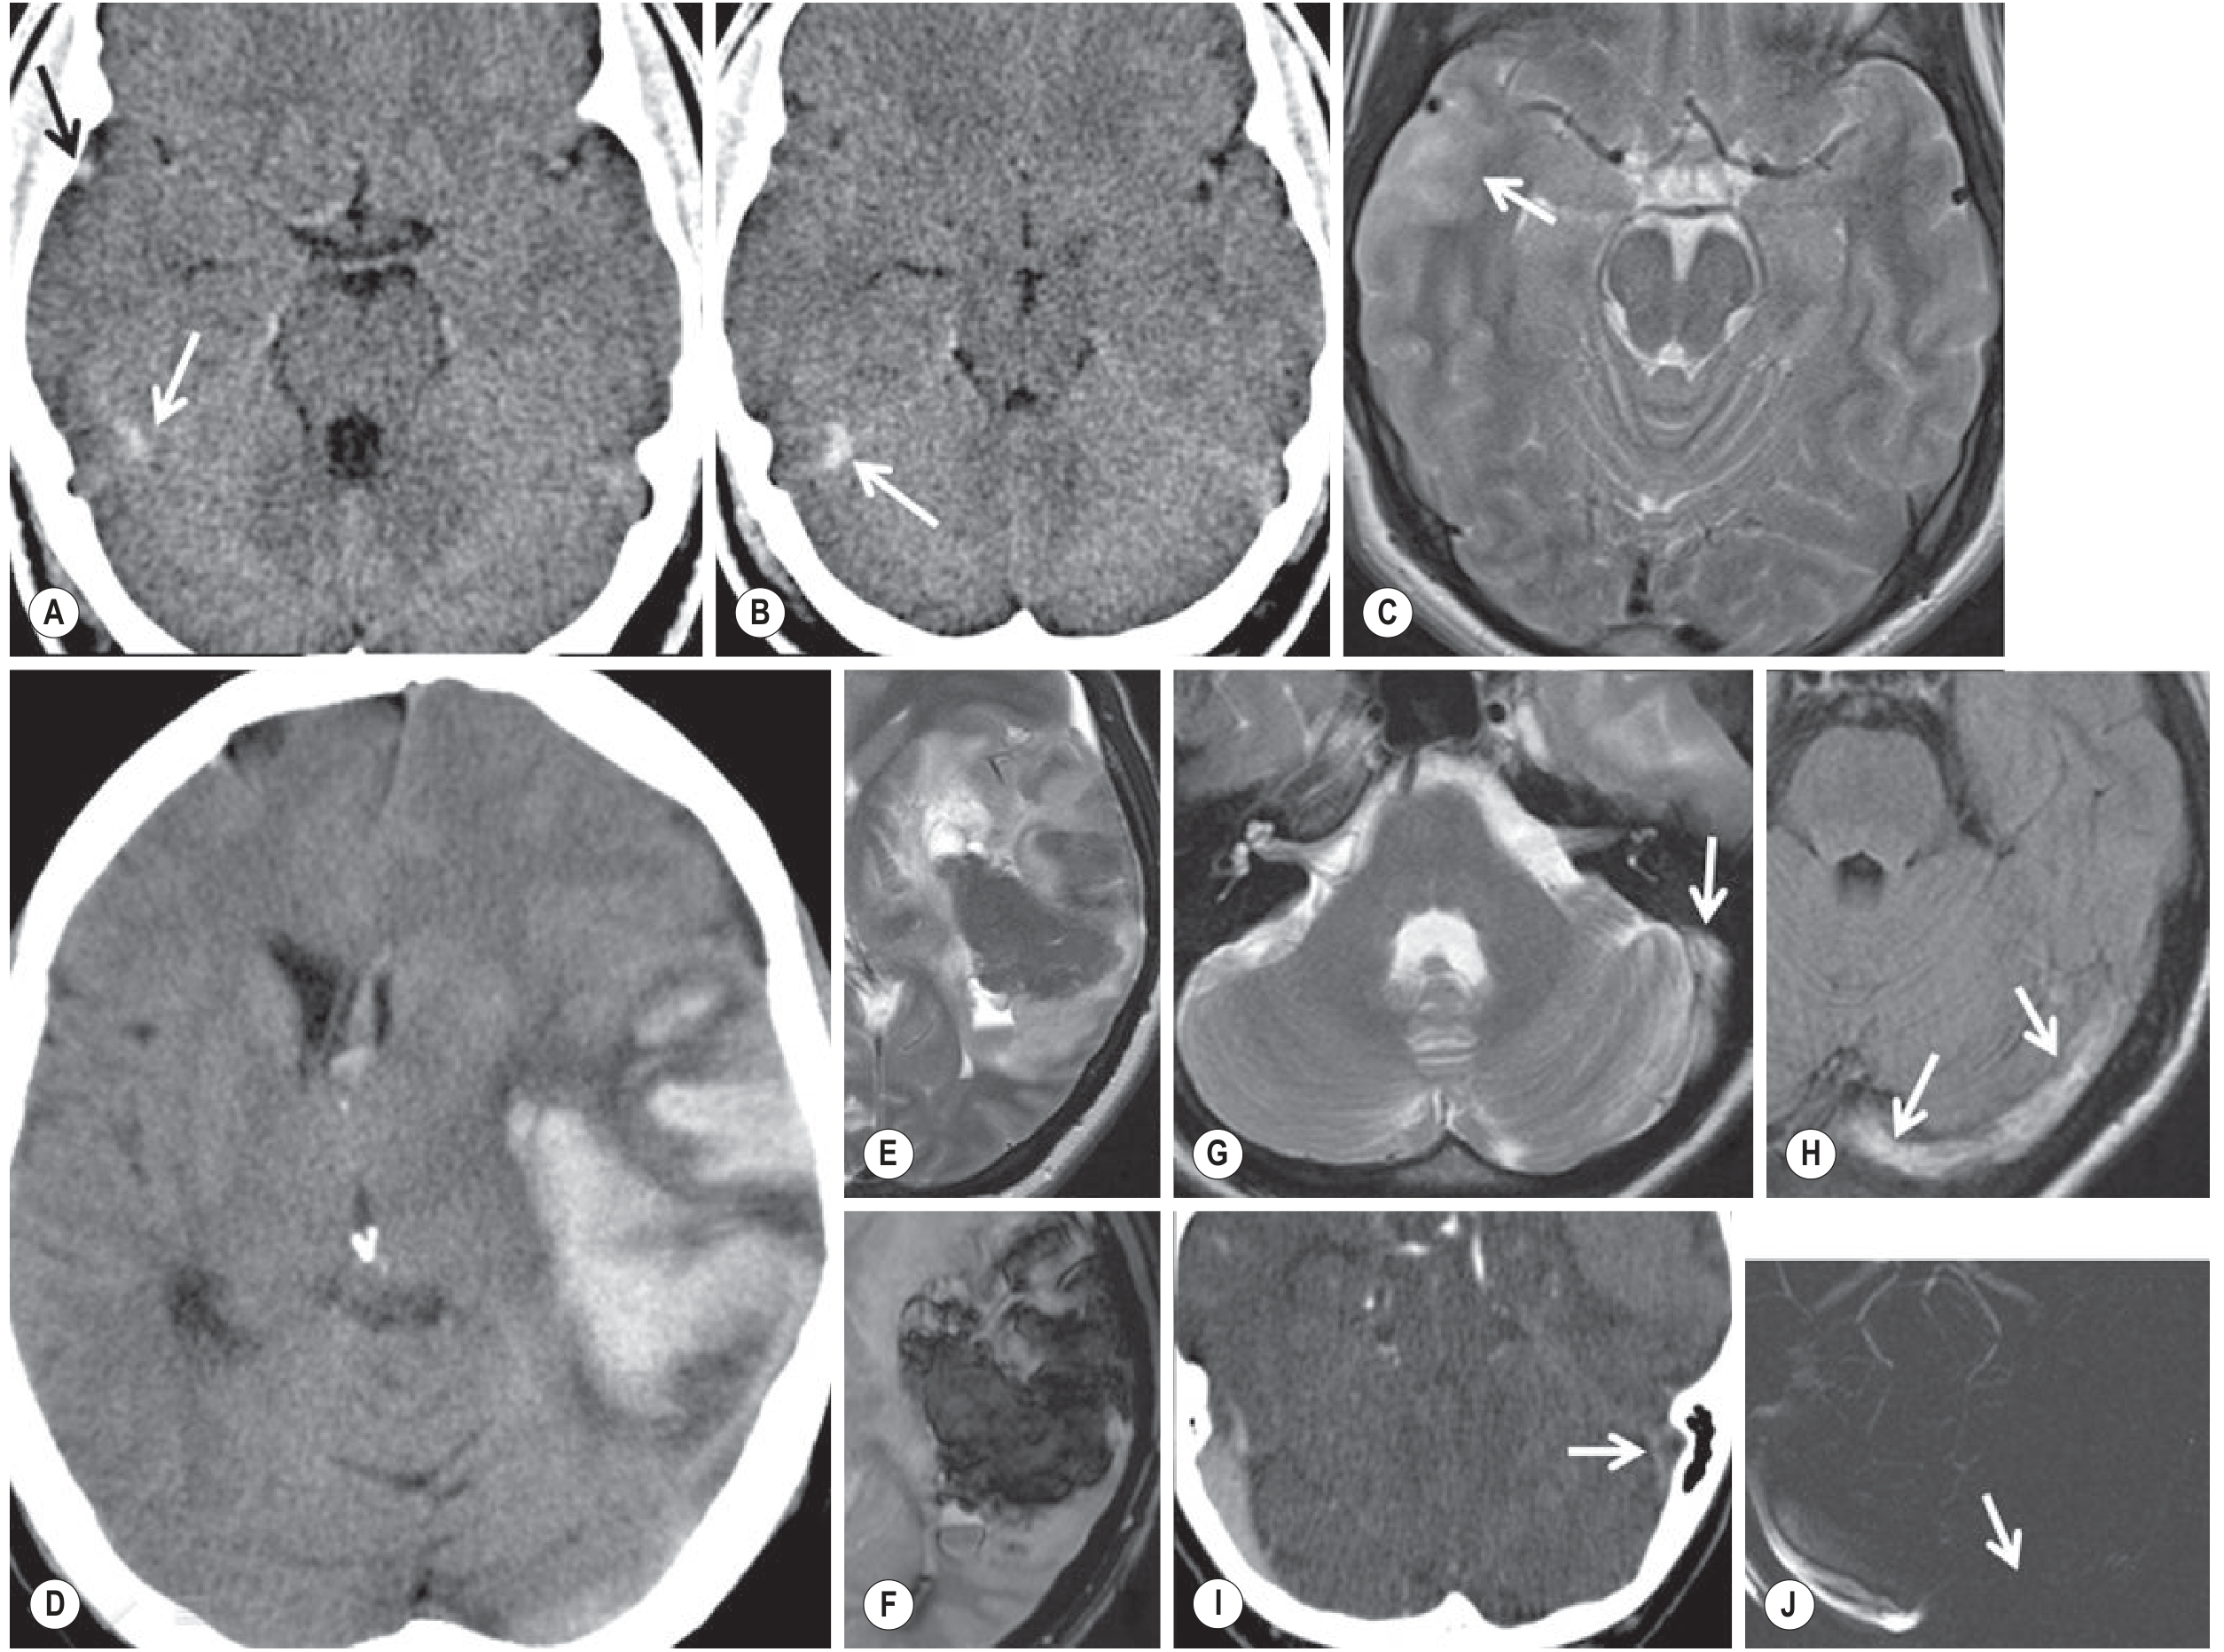

CVT imaging: CT and MRI findings including hemorrhagic infarcts, venous congestion, and parenchymal signal changes in cerebral venous sinus thrombosis

Fig. 56.28 — Cerebral Venous Thrombosis. CT (A, B, D) and MRI (C, E–J) demonstrating hemorrhagic infarcts, venous congestion, and parenchymal edema/signal abnormalities from Grainger & Allison's Diagnostic Radiology.